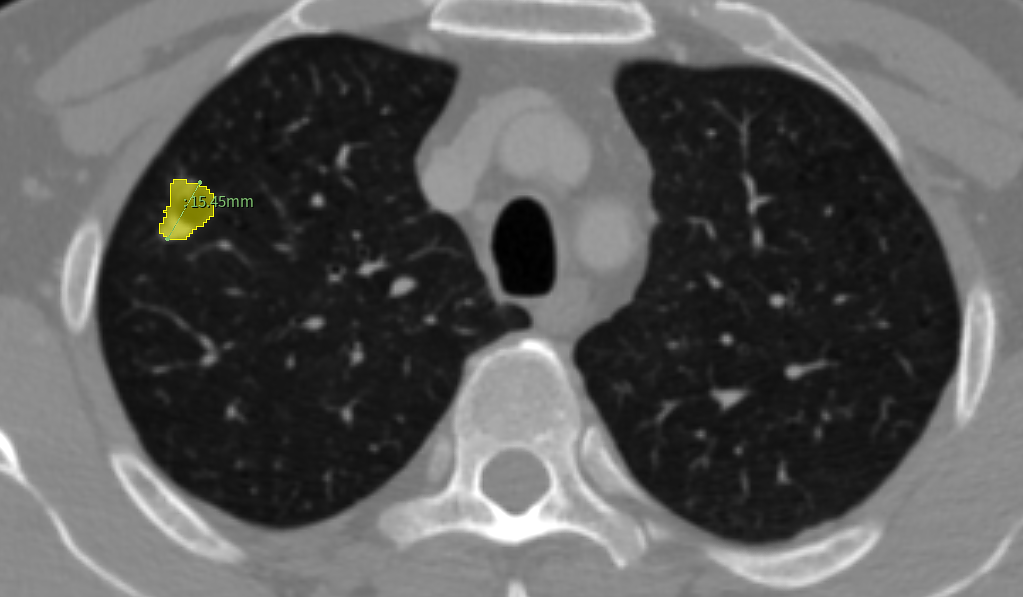

(CT扫描中,识别出1个结节)

患者的CT检查显示,结节直径1cm,靠近支气管。这一区域血管神经密集,传统二维影像只能呈现平面重叠图像,医生无法精准判断结节与两支支气管的空间位置关系,若贸然手术可能损伤气道或血管,导致气胸、出血等并发症,或因切除范围过大牺牲健康肺组织。